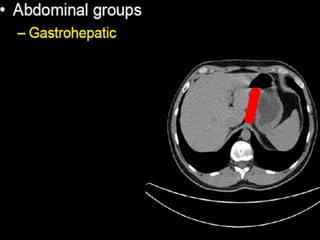

CT cross sectional anatomy.